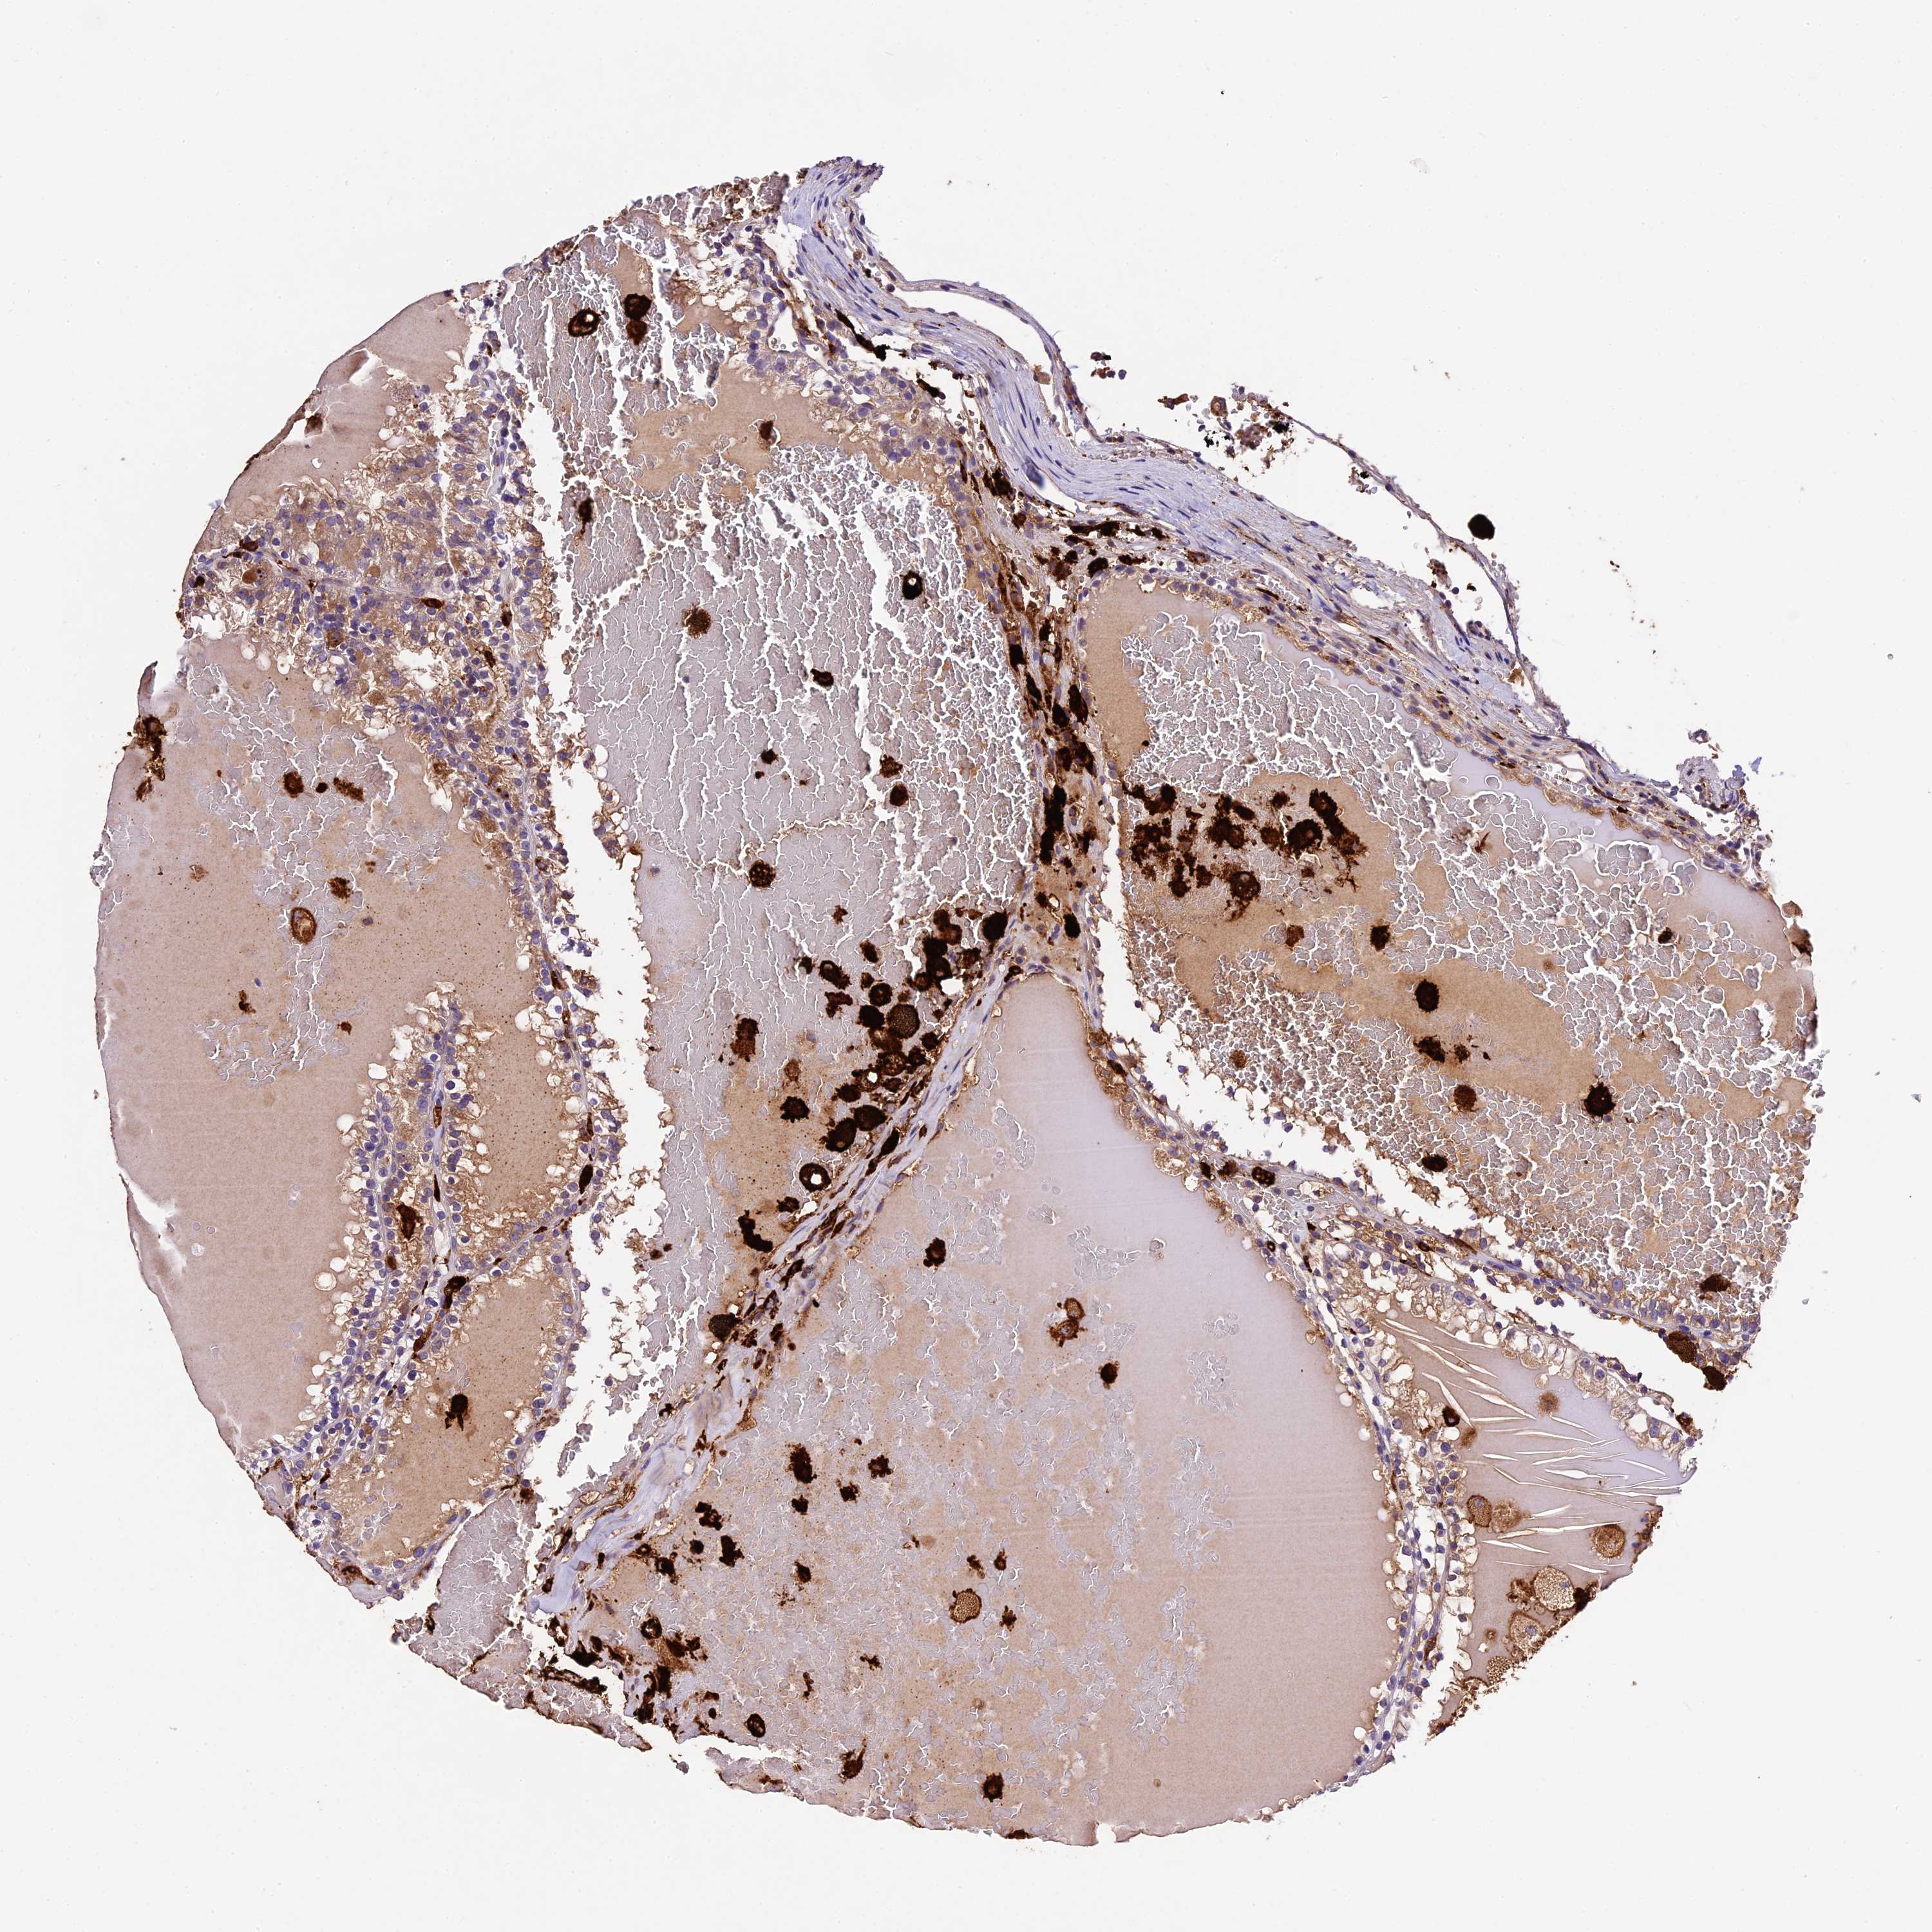

KIDNEY RENAL CLEAR CELL CARCINOMA (VALIDATION) - Interactive survival scatter ploti

The Survival Scatter plot shows the clinical status (i.e. dead or alive) for all individuals in the patient cohort, based on the same data that underlies the corresponding Kaplan-Meier plots. Patients that are alive at last time for follow-up are shown in blue and patients who have died during the study are shown in red.

The x-axis shows the expression levels (FPKM) of the investigated gene in the tumor tissue at the time of diagnosis. The y-axis shows the follow-up time after diagnosis (years). Both axes are complimented with kernel density curves demonstrating the data density over the axes. The top density plot shows the expression levels (FPKM) distribution among dead (red) and alive patients (blue). The right density plot shows the data density of the survived years of dead patients with high and low expression levels respectively, stratified using the cutoff indicated by the vertical dashed line through the Survival Scatter plot. This cutoff is automatically defined based on the FPKM cutoff that minimizes the p-score. The cutoff can be changed by dragging the vertical line or by entering a cutoff value in the square labeled "Current cut-off".

Under the Survival Scatter plot the p-score landscape (black curve; left axis) is shown together with dead median separation (red curve; right axis). Dead median separation is the difference in median mRNA expression between patients who have died with high and low expression, respectively. It is calculated as follows: median FPKM expression of dead patients with high expression - median FPKM expression of dead patients with low expression. This is intended to aid the user in visually exploring custom cutoffs and the associated p-scores and dead median separation.

Individual patient data is displayed and can be filtered by clicking on one or more of the category buttons on the top of the page. Categories describing expression level and patient information include: high, low, alive, dead, female, male and tumor stages. The scale of the x-axis can be toggled between linear and log-scale by clicking on the "x log" button. Mouse-over function shows TCGA ID, patient information and mRNA expression (FPKM) for each patient.

& Survival analysisi

Kaplan-Meier plots summarize results from analysis of correlation between mRNA expression level and patient survival. Patients were divided based on level of expression into one of the two groups "low" (under cut off) or "high" (over cut off). X-axis shows time for survival (years) and y-axis shows the probability of survival, where 1.0 corresponds to 100 percent.

CILP2 is not prognostic in Kidney Renal Clear Cell Carcinoma (validation)

TCGA RNA samplesi

RNA-seq data is reported as average FPKM (number Fragments Per Kilobase of exon per Million reads), generated by the The Cancer Genome Atlas (TCGA) .

Normal distribution across the dataset is visualized with box plots, shown as median and 25th and 75th percentiles. Points are displayed as outliers if they are above or below 1.5 times the interquartile range. FPKM values of the individual samples are presented next to the box plot.

Average pTPM 0.2

Number of samples 100